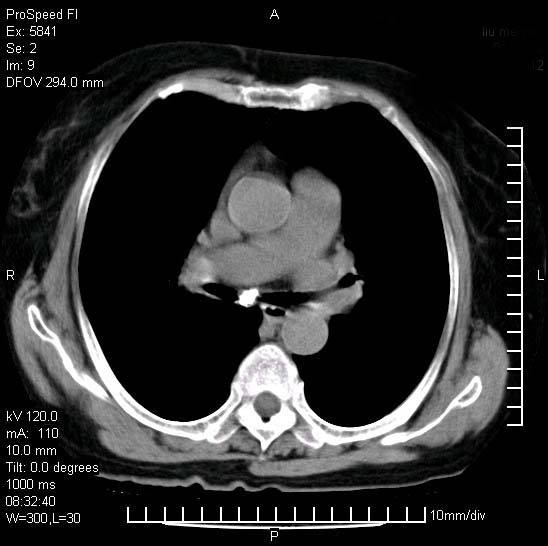

胸痛,咳嗽,气短一周,无发热。右上肺见一结节灶,边缘刺角,内见多个小钙化结节。考虑结核球?肿瘤? 余无异常没有上传。